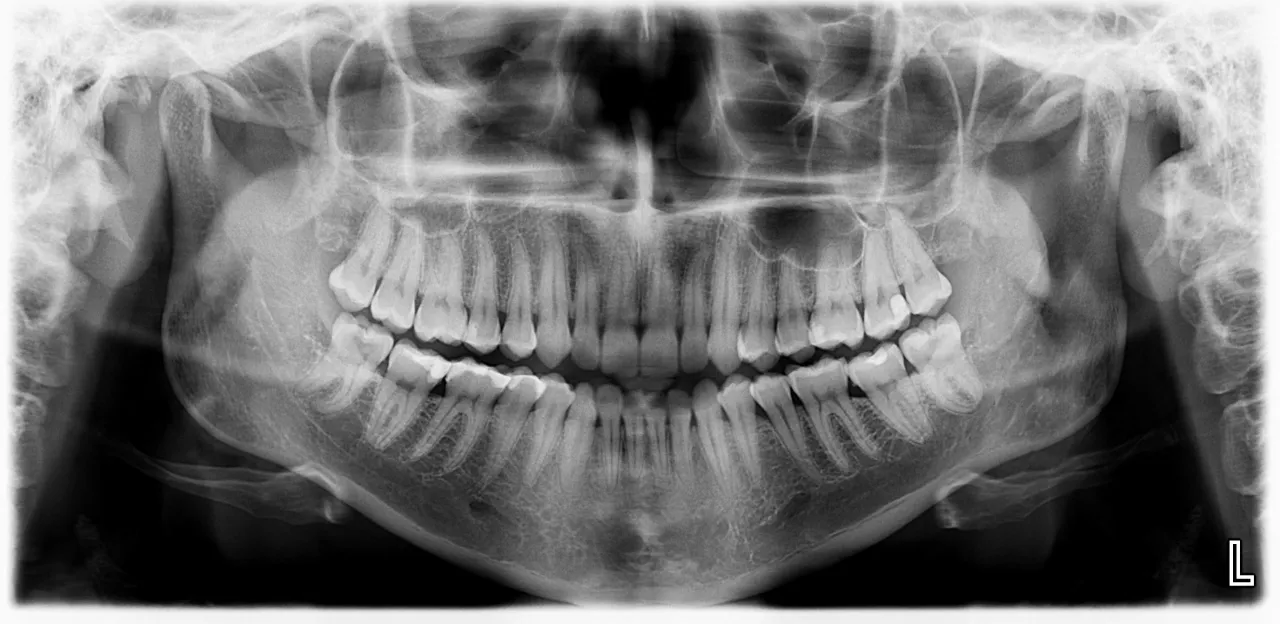

- Kluczowa w diagnostyce jest wizyta u stomatologa i wykonanie zdjęcia RTG (pantomogramu).

Kluczową rolę w diagnostyce problemów z zębami mądrości odgrywa radiologia. Najczęściej wykonywanym badaniem jest zdjęcie panoramiczne, czyli pantomogram. To właśnie na takim zdjęciu dentysta lub chirurg szczękowo-twarzowy może precyzyjnie ocenić położenie wszystkich zębów, w tym ósemek, nawet tych całkowicie zatrzymanych w kości. Pantomogram pozwala również na ocenę relacji zęba mądrości do ważnych struktur anatomicznych, takich jak kanał żuchwy, w którym przebiega nerw zębodołowy dolny, czy korzenie sąsiednich zębów. Dzięki temu można zaplanować ewentualne leczenie lub zabieg ekstrakcji z maksymalnym bezpieczeństwem dla pacjenta.